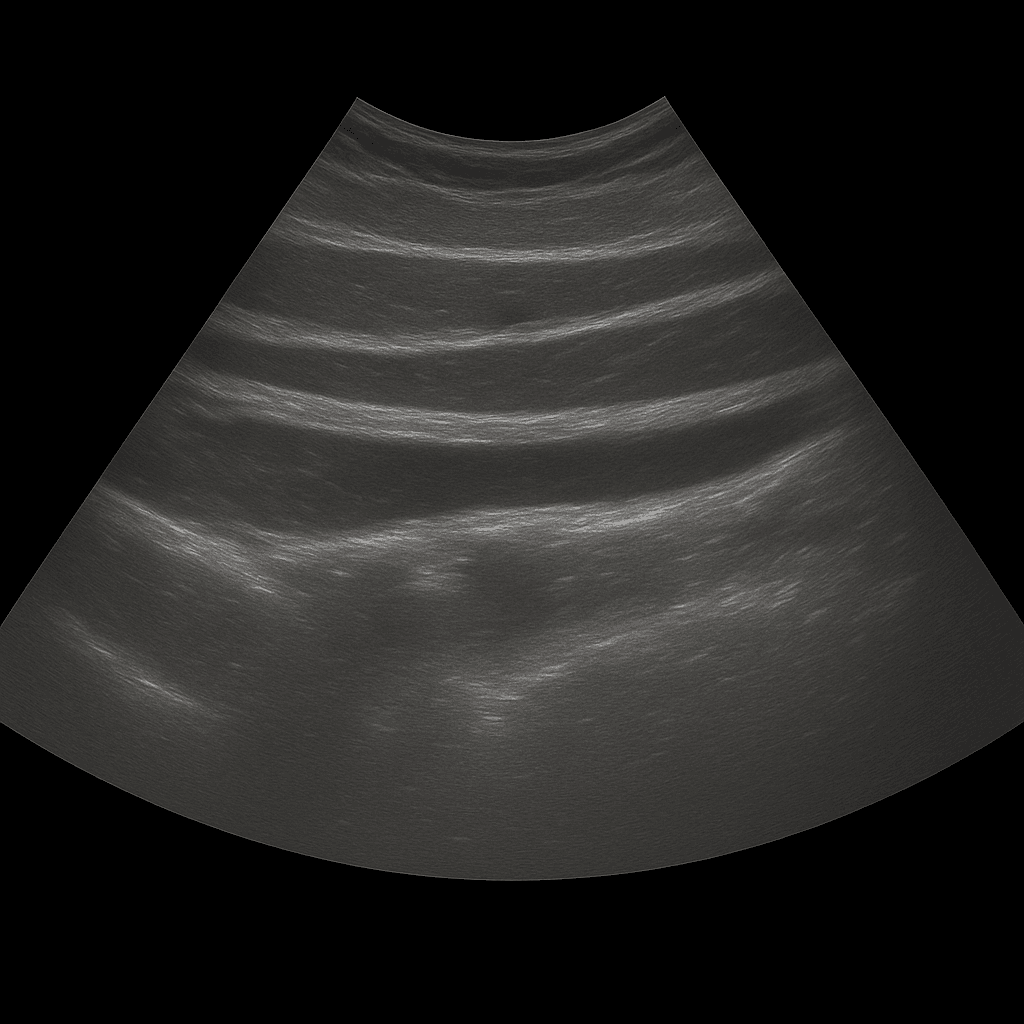

Ett ultraljud av bukväggen används för att undersöka hud, underhud och muskulatur i bukväggen. Undersökningen utförs av specialistläkare inom radiologi och ger detaljerade bilder i realtid som kan visa förändringar som orsakar smärta, svullnad eller synliga utbuktningar i buken. Ultraljud bukvägg används ofta vid misstanke om bråck, vätskeansamlingar, hematom eller andra förändringar i mjukdelarna.

Till skillnad från MR och DT, som används för att kartlägga djupare organ och strukturer i bukhålan, är ultraljud förstahandsvalet för att undersöka ytliga förändringar i bukväggen. Ultraljud visar muskulatur, vävnadslager och eventuella defekter i realtid – utan strålning eller kontrastmedel.

Undersökningen utförs medan du ligger på rygg. En gel appliceras på huden och läkaren för ultraljudsproben över det område där du har besvär. Bukväggen undersöks i olika plan, både vid vila och under lätt anspänning, vilket gör det möjligt att se eventuella bråck eller defekter som framträder när buken belastas.